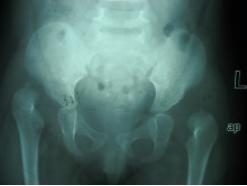

双侧髋关节脱位